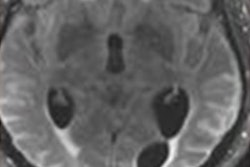

Monoclonal antibodies for Alzheimer's disease are a new class of drugs that have proven in clinical trials to reduce brain deposits of amyloid plaque, based largely on amyloid PET scans of patients before and after treatment. These deposits are associated with neurocognitive decline.